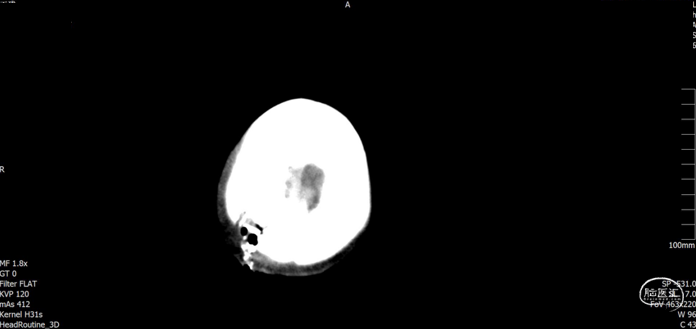

现病史:患者于入院前2小时在工地干活时被高空坠物砸伤头部(具体过程不详),伤后出现左侧肢体活动失灵,被同事送往我院急诊科就诊,入急诊时神志清醒,GCS15分,行颅脑CT提示:1. 右侧颞顶骨骨折,顶骨多发骨折并部分嵌插脑内;2. 右侧顶叶脑挫伤;3. 右侧额颞顶部硬膜下血肿;4. 蛛网膜下腔出血。急诊予以清创、止血及对症治疗。期间患者意识障碍加重呈嗜睡,GCS14分,我科急会诊后以“1. 开放性颅脑损伤特重型 1.1开放性颅内异物1.2脑挫裂伤1.3蛛网膜下腔出血1.4颞顶骨骨折(右);2. 偏瘫(左)”收住入院。自发病来,患者暂无抽搐、晕厥等症状,小便失禁。

入院查体:右顶部头皮见长约2.0cm开放性伤口,出血并脑脊液漏出,颅骨嵌入。神志嗜睡,GCS评分:E3+V5+M6=14分。双侧瞳孔等大正圆,直径均约3.0mm,直、间接对光反射灵敏。左侧上下肢肌力约I/0级,右侧上下肢肌力约IV/IV级。

入院检查

![]()